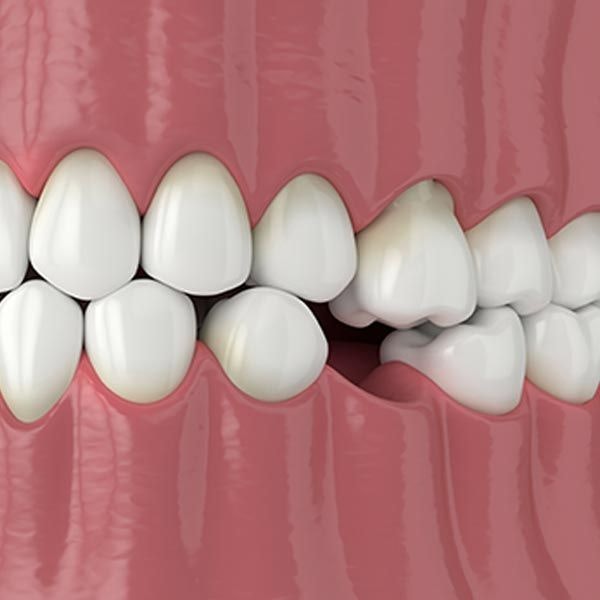

View on GoogleWisdom Teeth Extraction Can Prevent Further Damage

misalignment. Removing them promptly is crucial to preventing further issues

like periodontal disease and cavities.